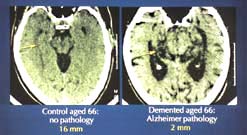

|  |  | | Changes in the brain due to AD | Alzheimer’s Disease

Alzheimer’s Disease is one of the commonest degenerative mental illnesses. It’s estimated that up to 700,000 in the UK suffer from it, and as the population ages, the figure is expected to rise to about 850,000 by 2020. Caring for people with Alzheimer’s Disease costs the UK over £1billion a year.

In the first of a new series of Frontiers, Peter Evans talks to doctors and researchers about our current state of knowledge of Alzheimer’s Disease. We know that tangles of fibrous tau protein build up inside the nerve cells, and that amyloid plaques form in the synapses between cells. But while therapies that slow the rate of memory loss are now available, we’re still a long way from discovering the mechanism that triggers the onset of Alzheimer’s Disease.